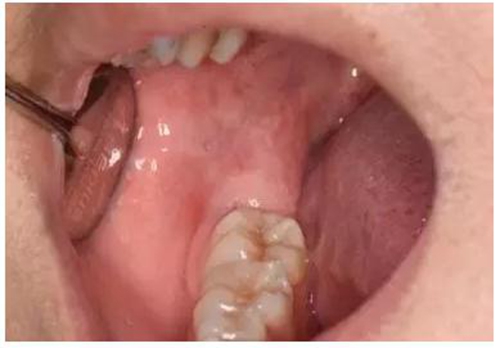

圖3.術(shù)前的口內(nèi)觀:48看不到,47遠(yuǎn)中有深盲袋、可探及48牙冠